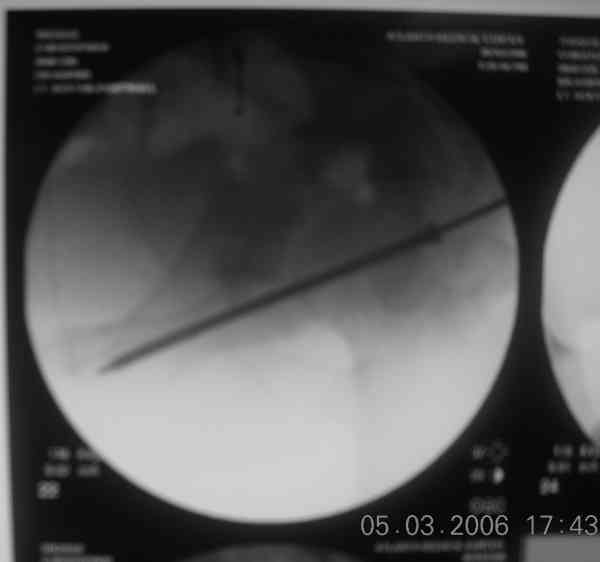

For this fracture pattern, I have had good luck with fluoro guided anterior column screw first.

pt supine helps get the best fluoro images. then cut the guide wire below the skin and leave it in place along with the anterior column screw. staple the small incision closed and cover with ioban. then reposition, remove ioban, reprep/drape pt in lateral decub for KL approach.

sometimes the anterior column screw needs to be backed out to help get the best reduction of posterior column. with guide wire in place this is fairly easy, the fracture will rotate around the wire, and the anterior column screw can be readvanced with confidence it is within bone. I have intra-op photos on office computer if interested.